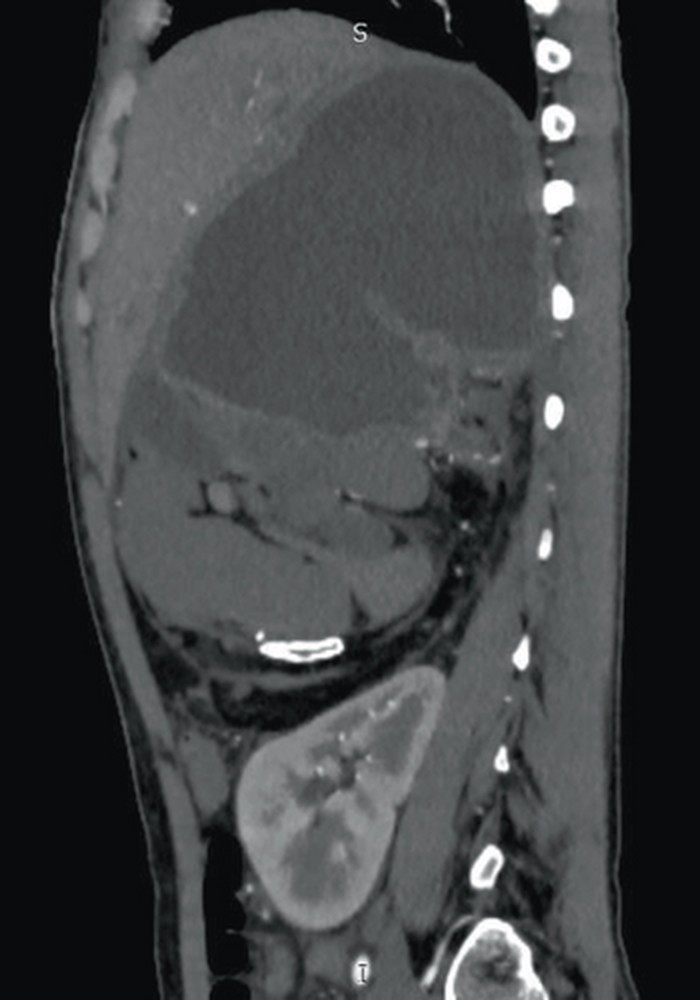

Seorang wanita 21 tahun datang ke bedah rawat jalan (OPD) dengan riwayat klinis benjolan di perut kanan atas selama 6-7 tahun, yang terus membesar disertai rasa nyeri. Ternyata ditemukan komponen jaringan lunak janin yang berukuran 22,5 x 14,1 x 12,5 cm. (Foto: Case Reports in Radiology.)